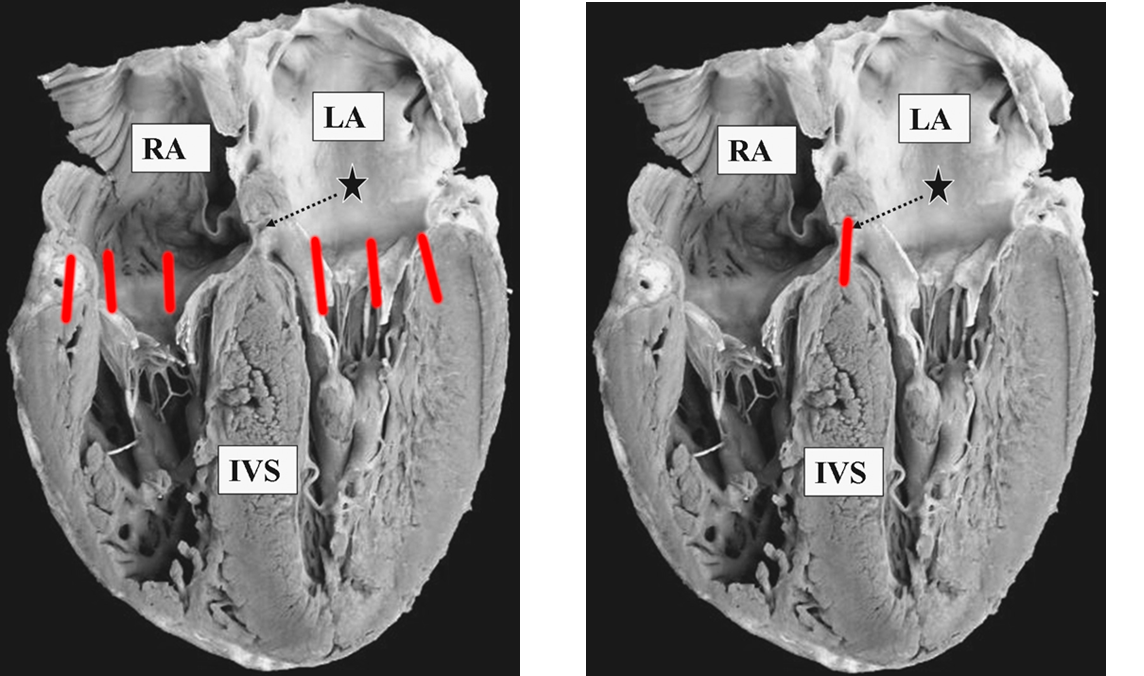

Activation after LBB transection

lbbb_activation.png

VENEROSE RS, SEIDENSTEIN M, STUCKEY JH, HOFFMAN BF. Activation of subendocardial Purkinje fibers and muscle fibers of the left septal surface before and after left bundle branch block. Am Heart J. 1962 Mar;63:346-61

lbbb_activation.jpeg